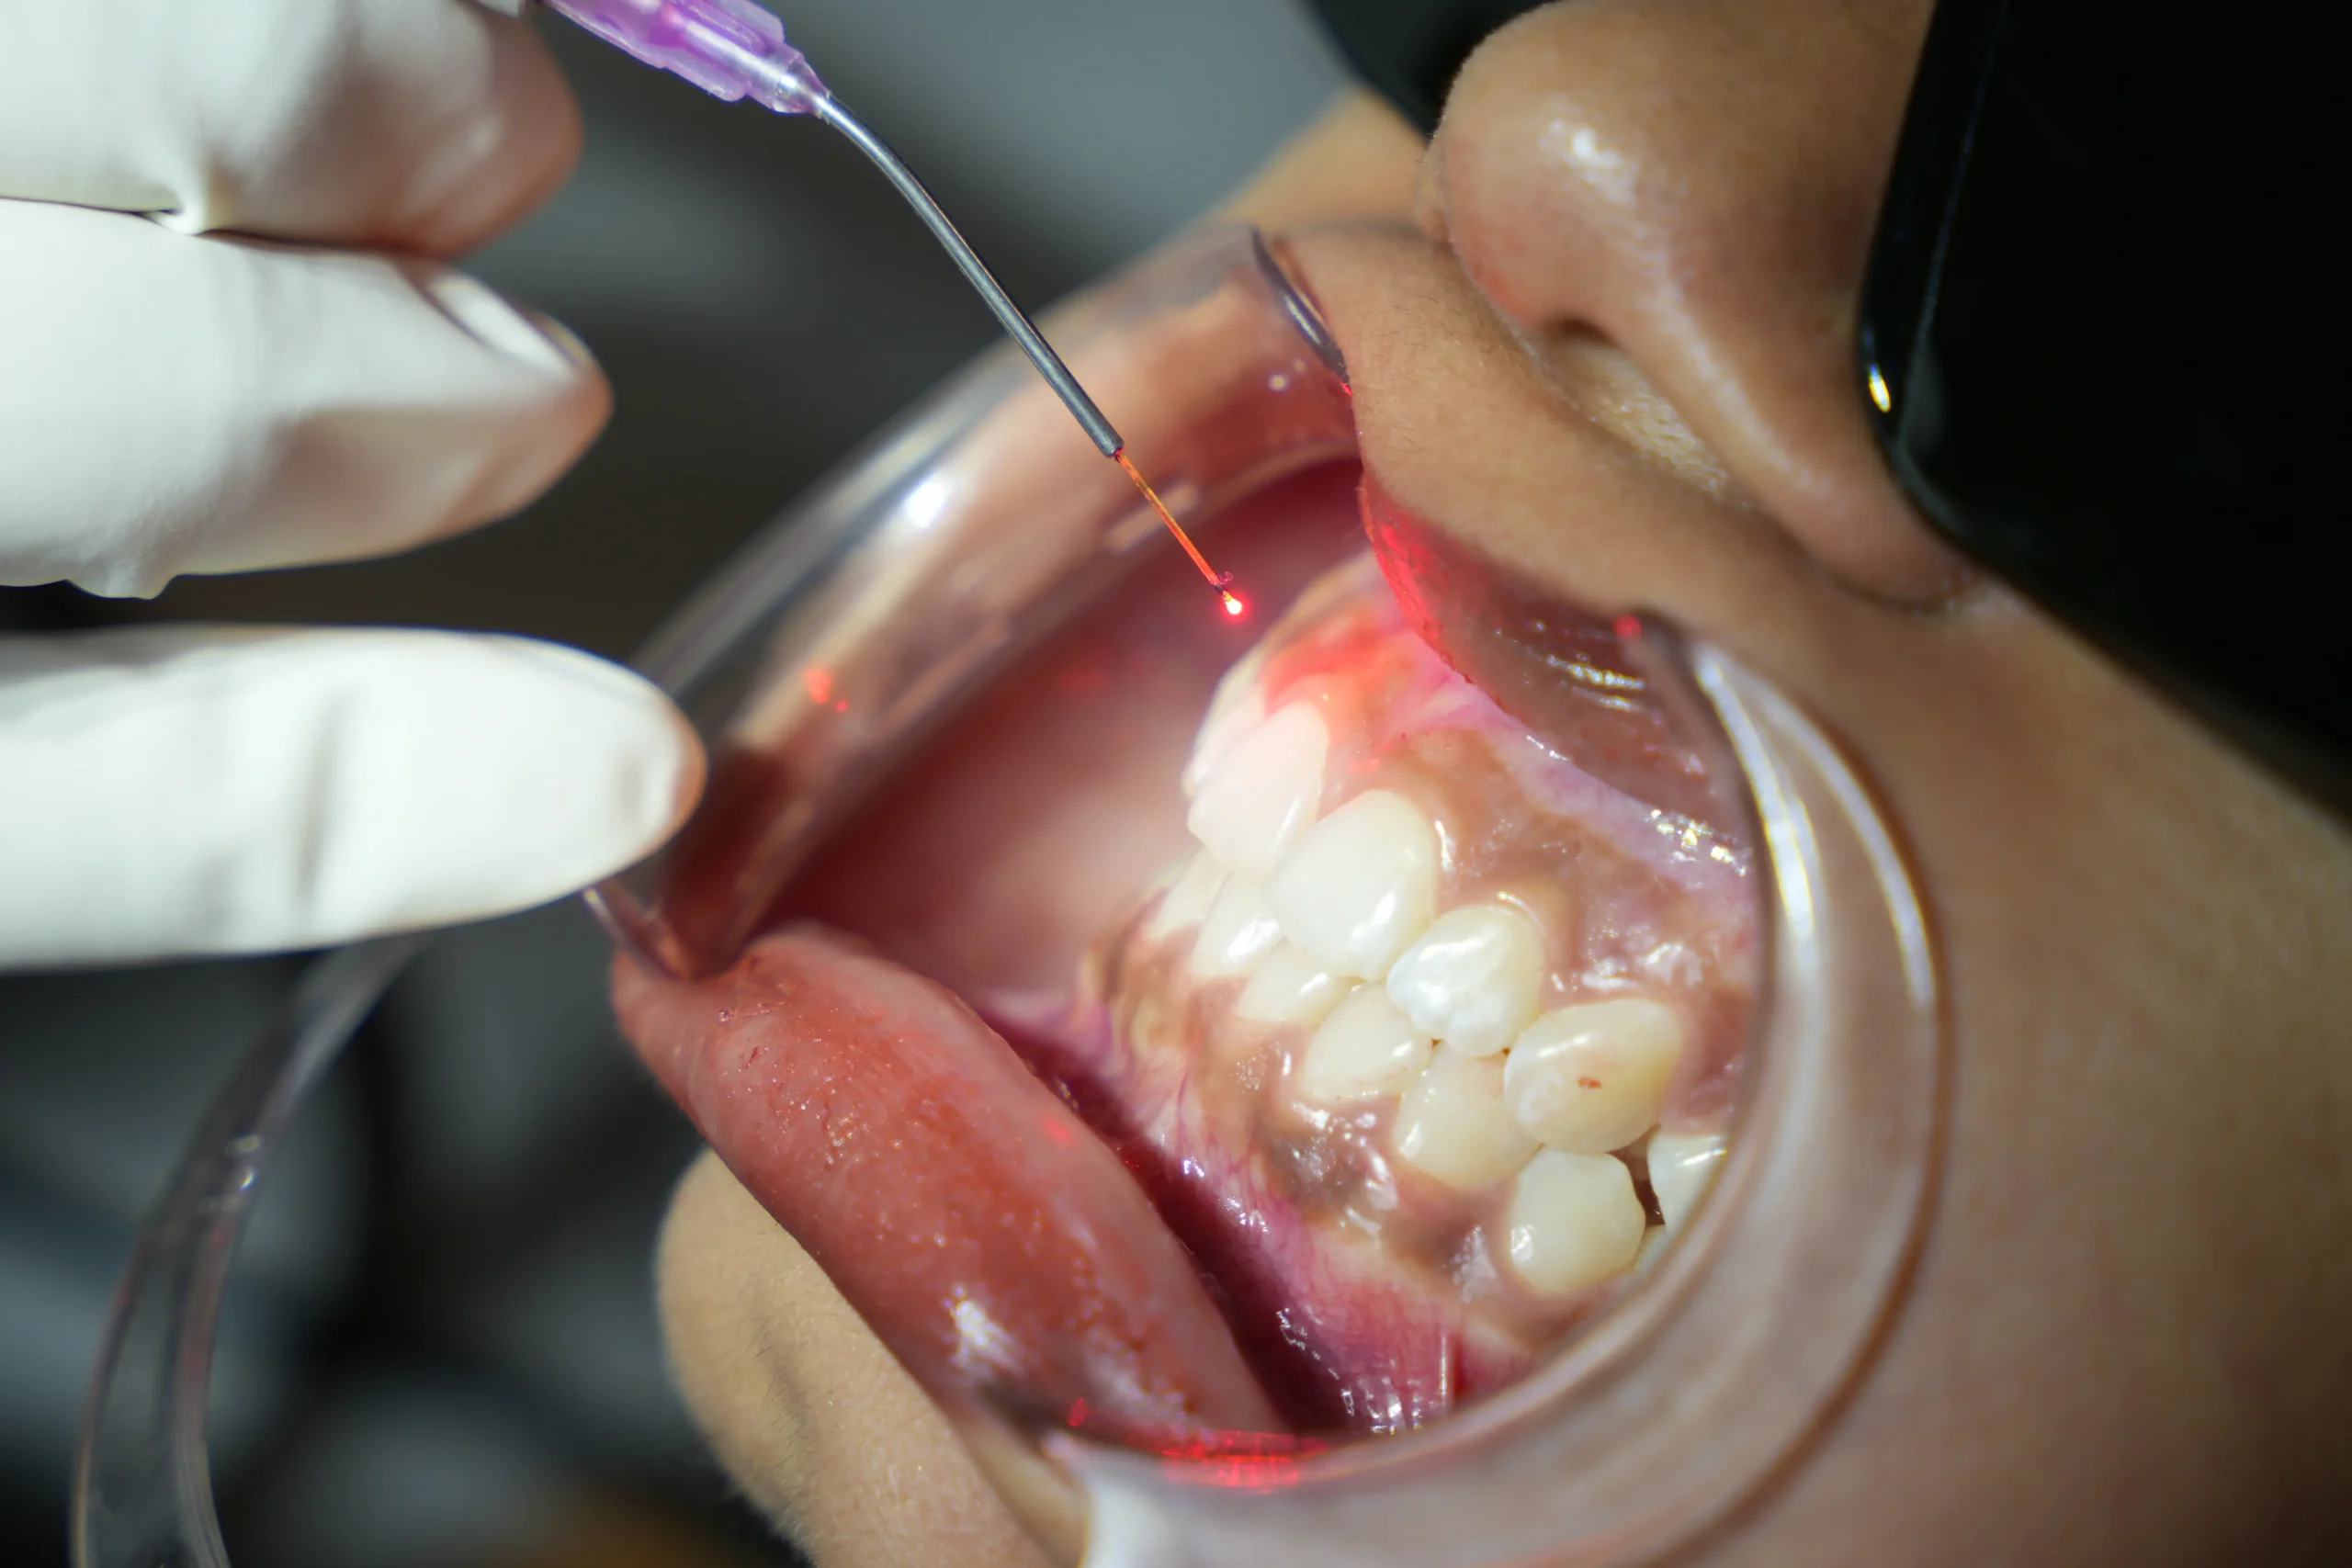

The treatment area is carefully cleaned and prepared. Protective eyewear is provided for eye safety during laser use, and in most cases, little to no anaesthesia is required.

Focused laser energy is used to gently reshape, remove, or disinfect tissue with high precision.

Most procedures have minimal bleeding and swelling, allowing you to resume daily activities quickly.